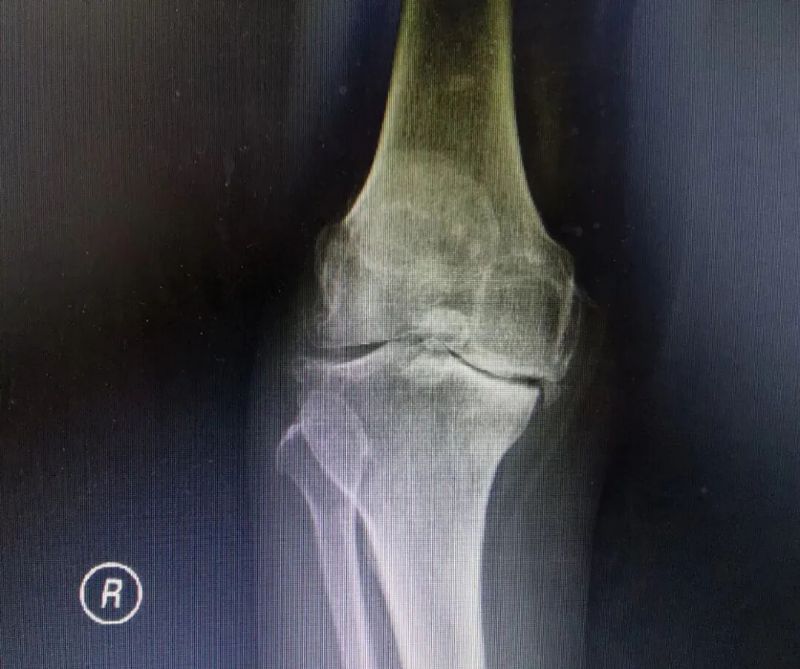

影像學(xué)檢查是診斷的重要手段。X線檢查就像給關(guān)節(jié)拍了一張“照片”,能夠清晰地顯示關(guān)節(jié)間隙變窄、骨質(zhì)增生、軟骨下骨硬化等典型表現(xiàn)。而MRI檢查則更像是一部“高清攝像機”,能更清晰地觀察關(guān)節(jié)軟骨、半月板、滑膜等軟組織的病變情況,為醫(yī)生提供更準(zhǔn)確的診斷依據(jù)。